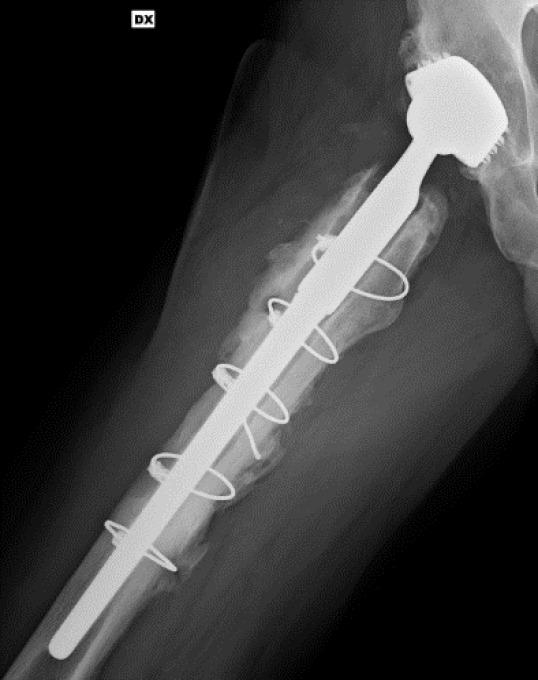

模块化牢固固定型髋关节翻修柄骨折:一例报告及文献综述

Modular Well-Fixed Hip Revision Stem Fracture: A Case Report and Literature Review.

This study presents a case of repeated prosthetic fractures in a modular hip prosthesis in a 56-year-old male patient. After the initial implantation of a modular total hip prosthesis in 2006, the patient experienced two instances of prosthetic implant fractures over seventeen years. In this study, we analyze the clinical case, explore potential underlying causes of this complication, and delve into current indications and strategies for the revision of fractured prosthesis stems. The discussion is informed by a literature review and underscores the significance of selecting appropriate revision techniques to address this challenge.

摘要

本研究报告了一例56岁男性患者模块化髋关节假体反复发生假体骨折的病例。2006年首次植入模块化全髋关节假体后,该患者在十七年中经历了两次假体植入物骨折。在本研究中,我们分析了该临床病例,探讨了这种并发症的潜在根本原因,并深入研究了目前骨折假体柄翻修的适应症和策略。讨论以文献综述为依据,并强调选择合适的翻修技术来应对这一挑战的重要性。